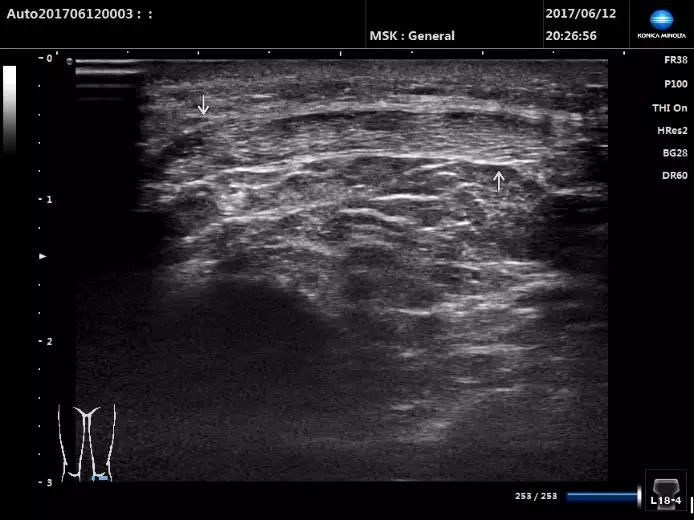

超聲掃查髕腱

盡管長軸切面為檢查髕腱的主要檢查切面,但有時髕腱的局灶性病變并不位于髕腱的中線位置。所以我們還應進行短軸切面掃查以避免髕腱邊緣病變的漏掃。